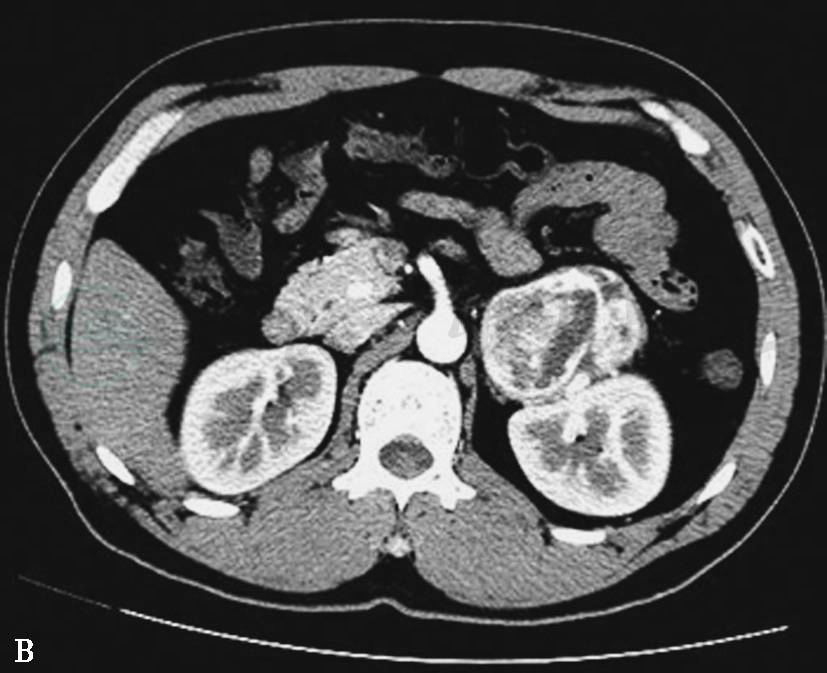

图11左侧肾上腺良性嗜铬细胞瘤

A~C.CT平扫、动脉期及静脉期示左侧肾上腺瘤体,平扫密度欠均匀,动脉期实性部分不均匀明显强化,呈斑点状、小片状,类似花斑脾样强化;静脉期进一步强化,坏死区域始终未强化